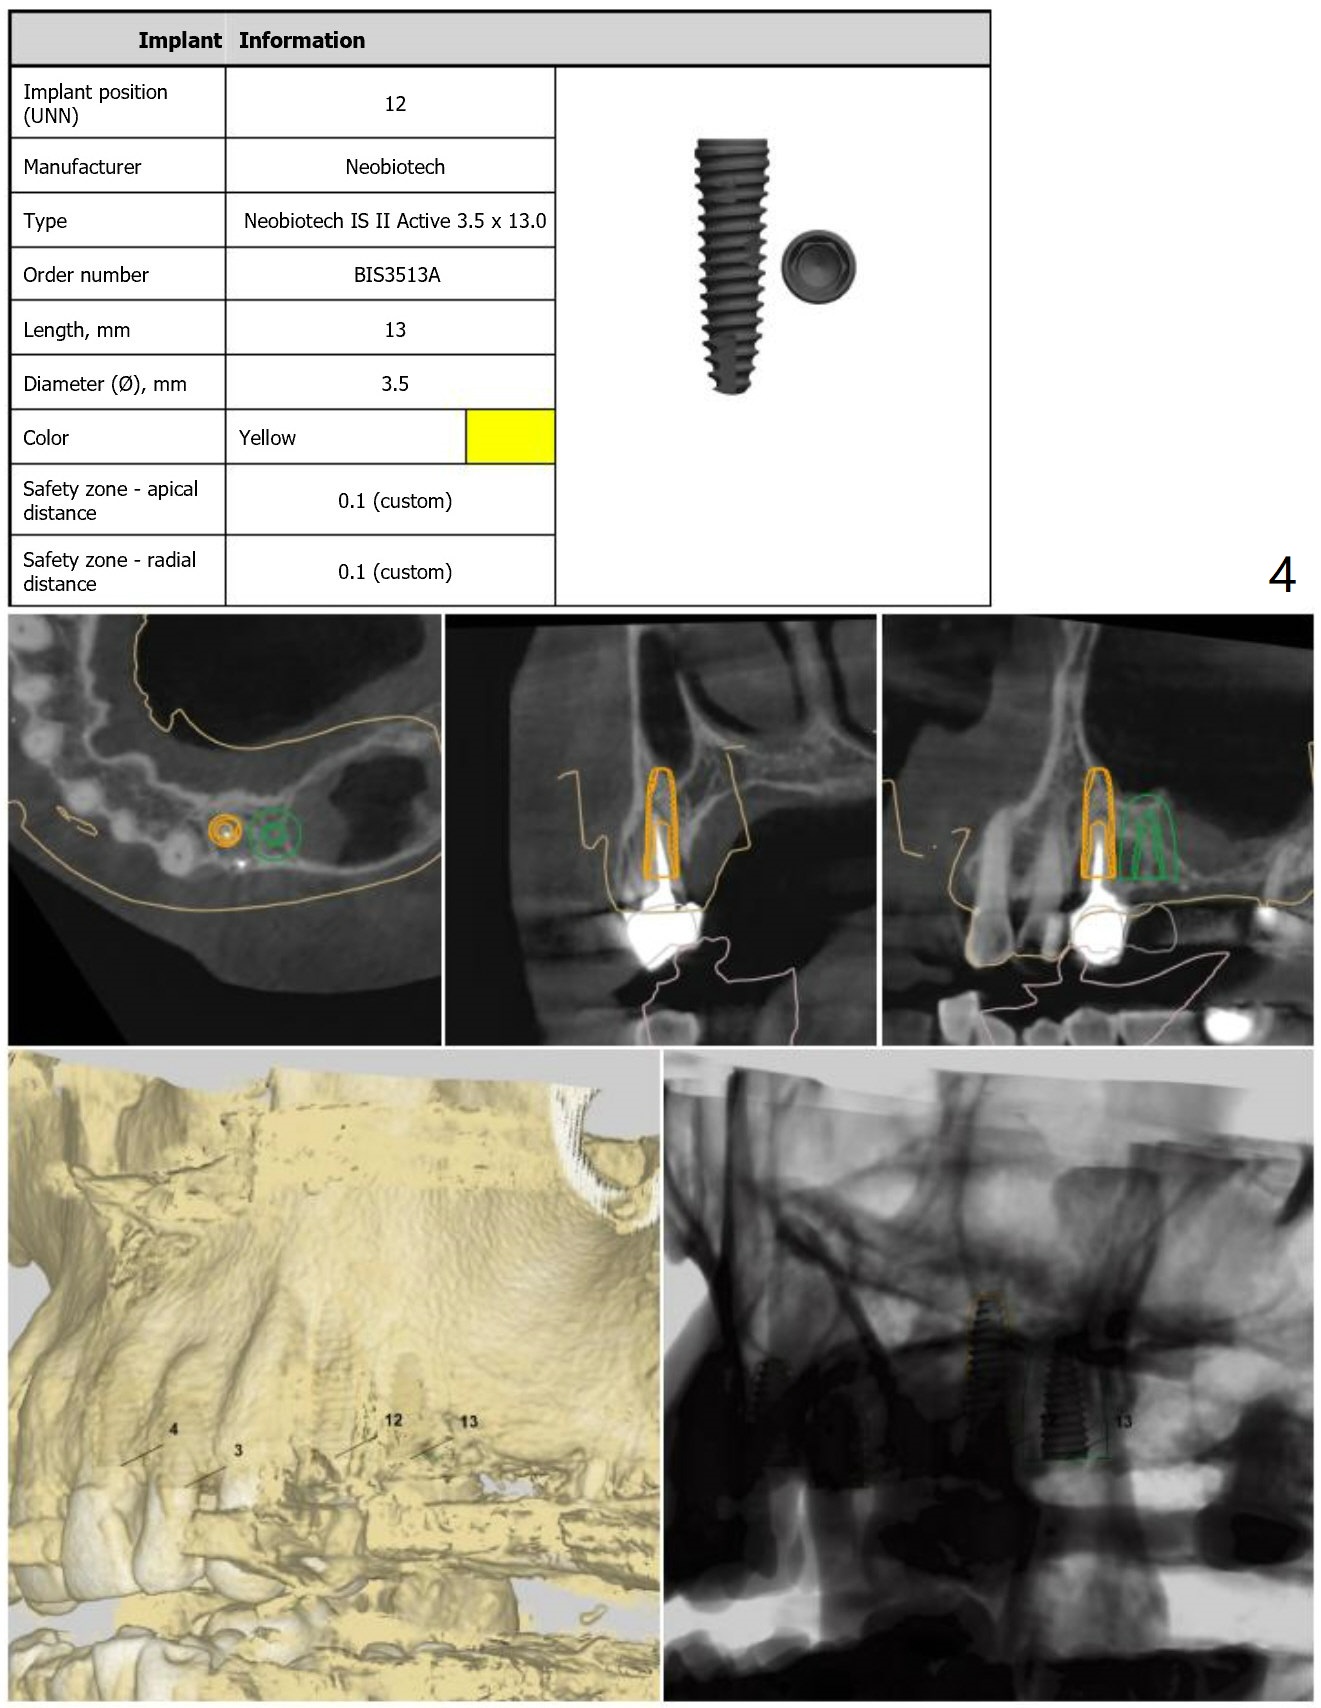

Guide for Sinus Lift

Return to Upper Arch Immediate Implant, Trajectory, No Antibiotic